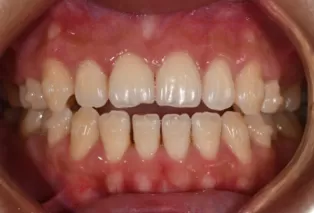

Intraoral photos after treatment